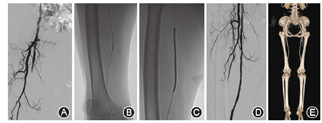

所有患者术前均常规生化检验,门诊检查ABI、血管彩超及CT血管造影(CTA)证实为下肢动脉狭窄或粥样硬化病变。无严重的心、肺、肝、肾功能不全以及出血和脑梗死风险,并同意接受药物球囊扩张术。数字减影血管造影(DSA)下选择合适的穿刺入路(对侧或同侧股动脉),若股动脉入路不佳,则选左侧肱动脉穿刺。穿刺点常规消毒铺巾,以2%的利多卡因5 ml于腹股沟区拟穿刺点局部麻醉,结合术前CTA图像明确诊断并近一步对手术方案进行评估与完善。以Sedinger技术穿刺动脉成功后,引入Simon、Cobra导管及泥鳅导丝,翻山进入对侧闭塞狭窄的病变动脉。用高压注射器进行造影,显示靶血管病变情况。置换翻山鞘,用V18/14导丝配合CX1开通导丝成功开通病变段后,根据术中造影显示的病变血管的长度、直径和位置选择合适规格的普通球囊逐级预扩狭窄或闭塞动脉2~3 min。若预扩后造影显示狭窄程度≤50%或存在非限流性夹层(不影响血流动力学),则选择合适相同规格(普通球囊与药涂球囊直径比为1∶1,长度不能超过DCB长度)的药涂球囊(北京先瑞达医疗科技公司)扩张3 min。若普通球囊预扩后显示狭窄仍>50%或存在限流性夹层(影响血流动力学),改用金属裸支架补救术。如再次造影显示造影剂通过顺畅,术毕拔管,穿刺点按压10 min,压迫器压迫止血,患者安返病房。图1为DCB治疗长段下肢动脉病变手术影像资料。

注:A图:术中DSA提示右侧股浅动脉长段闭塞;B图:导管配导丝开通病变;C图:术中用5 mm×200 mm药涂球囊扩张;D图:术后造影提示血流通畅;E图:术后12个月复查CTA提示右侧股浅动脉通畅;DSA:数字减影血管造影;CTA:CT血管造影